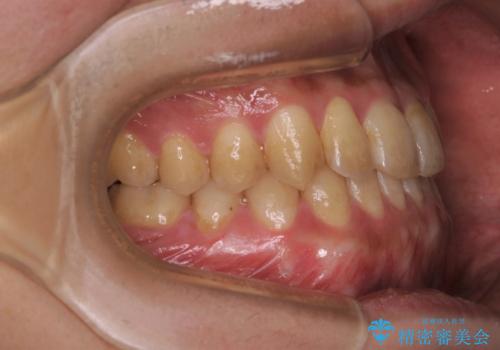

- 矯正治療が終わったので歯のクリーニングを希望され来院しました。

PMTC60分コースを行いました。

全体の歯の面に着色がついていました。PMTCを定期的に行うことにより、毎日の歯磨きやお食事によって傷ついた歯をツヤツヤでなめらかな歯にしてくれます。ですので着色が付着しにくい歯にすることができます。